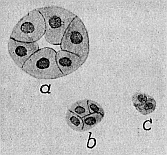

Da haben wir eine ganze Menge darüber erfahren, wie die Organe im Alter verändert werden. Aber all das können wir erst verstehen, wenn wir das Mikroskop zu Hilfe nehmen, die Organe alter Leute mikroskopisch untersuchen. Sehen wir uns z. B. ein Stückchen Niere von einem Menschen an, der aus Altersschwäche gestorben ist (Abb. 17). Da sind an einer Stelle noch gut erhaltene Nierenzellen zu sehen, die ein Nierenkanälchen bilden, wie es sich für eine normale Niere nicht besser gehörte. Aber wir finden auch Nierenkanälchen, die ganz zusammengefallen sind, wo sogar die Lichtung der Kanälchen geschwunden ist. Die Zellen dieser Kanälchen sind verkleinert, „atrophisch“, wie man sagt. Diese Zellen haben einen Altersschwund erfahren. Genau so ist es mit den Zellen der Leber, der Drüsen, des Gehirnes und der Organe sonst. Weil die Zellen der Organe klein, atrophisch geworden sind, sind eben bei dem alten Menschen die Organe kleiner als in jüngeren Jahren. Es findet also im Alter eine Atrophie der Zellen statt, ein Schwund der lebendigen Zellsubstanz. Der Schwund der lebendigen Substanz der Zellen kennzeichnet alle Organe des gealterten Körpers.

Abb. 17. Horizontalschnitte durch Nierenkanälchen aus der Niere eines alten Menschen. a mit noch gut erhaltenen Zellen; man sieht hier deutlich die Lichtung des Nierenkanälchens. b und c mit atrophischen Zellen: die Kanälchen sind zusammengefallen, eine Lichtung ist nicht mehr vorhanden. Stark vergrößert. Nach Ziegler. Etwas schematisiert.